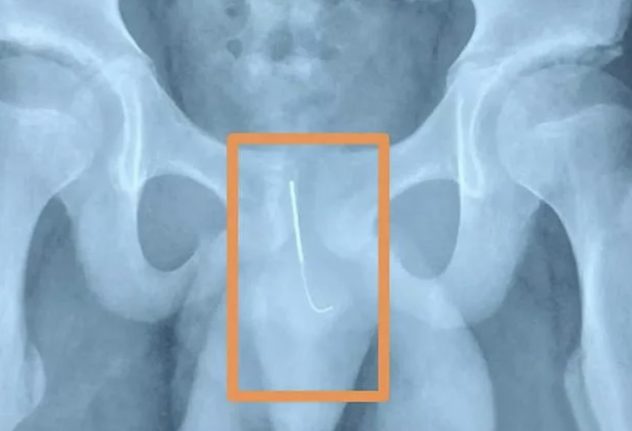

Xiaolongista, Kiinasta kotoisin oleva 12-vuotias poika joutui leikkaukseen laitettuaan 10 senttimetriä pitkän akupunktioneulan penikseensä. Äiti oli seuraavana aamuna huomannut poikansa kävelevän erikoisesti ja vienyt hänet sairaalaan, paikallinen media uutisoi.

Poika kertoi myöhemmin yrittäneensä pysyä hereillä kotiläksyjen aikana, jonka vuoksi hän työnsi 10 sentin neulan virtsaputkensa sisälle.

Poika kuljetettiin Xiaolongin lastensairaalaan vasta 15 tuntia tapahtuman jälkeen, sillä on oli liian nolostunut kertomaan totuutta. Sairaalaan johtava urologi kertoi pojan kärsineen äärimmäisen kovista kivuista samalla, kun hänen vanhempansa olivat todella huolissaan.

”Pojalla oli vaikeuksia pissata, sillä neula oli lävistänyt hänen virtsaputkensa ja mennyt vaarallisen lähelle virtsarakkoa”, lääkäri kertoo ja jatkaa:

”Hän oli vaarassa saada tulehduksen ja neula olisi voinut liikkuessaan repiä auki virtsarakon tai verisuonia.

Kirurgit onnistuivat poistamaan neulan onnistuneesti kaksi tuntia kestäneen leikkauksen aikana ja poika toipui täysin.